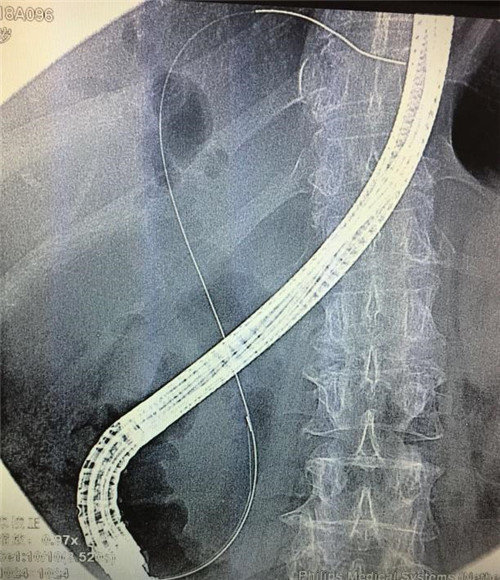

经过多个科室的配合,在介入科X线机下,曹鹏医生于十二指肠镜下顺利将导丝插入患者胆管内,注入二氧化碳气体造影,X线下见患者肝内外胆管扩张,胆管末端明显有占位性病变,患者胆管末端因肿瘤压迫,非常狭窄,经过多级扩张后,顺利为患者置入胆道支架。手术非常顺利,患者生命体征平稳,大家都松了口气。